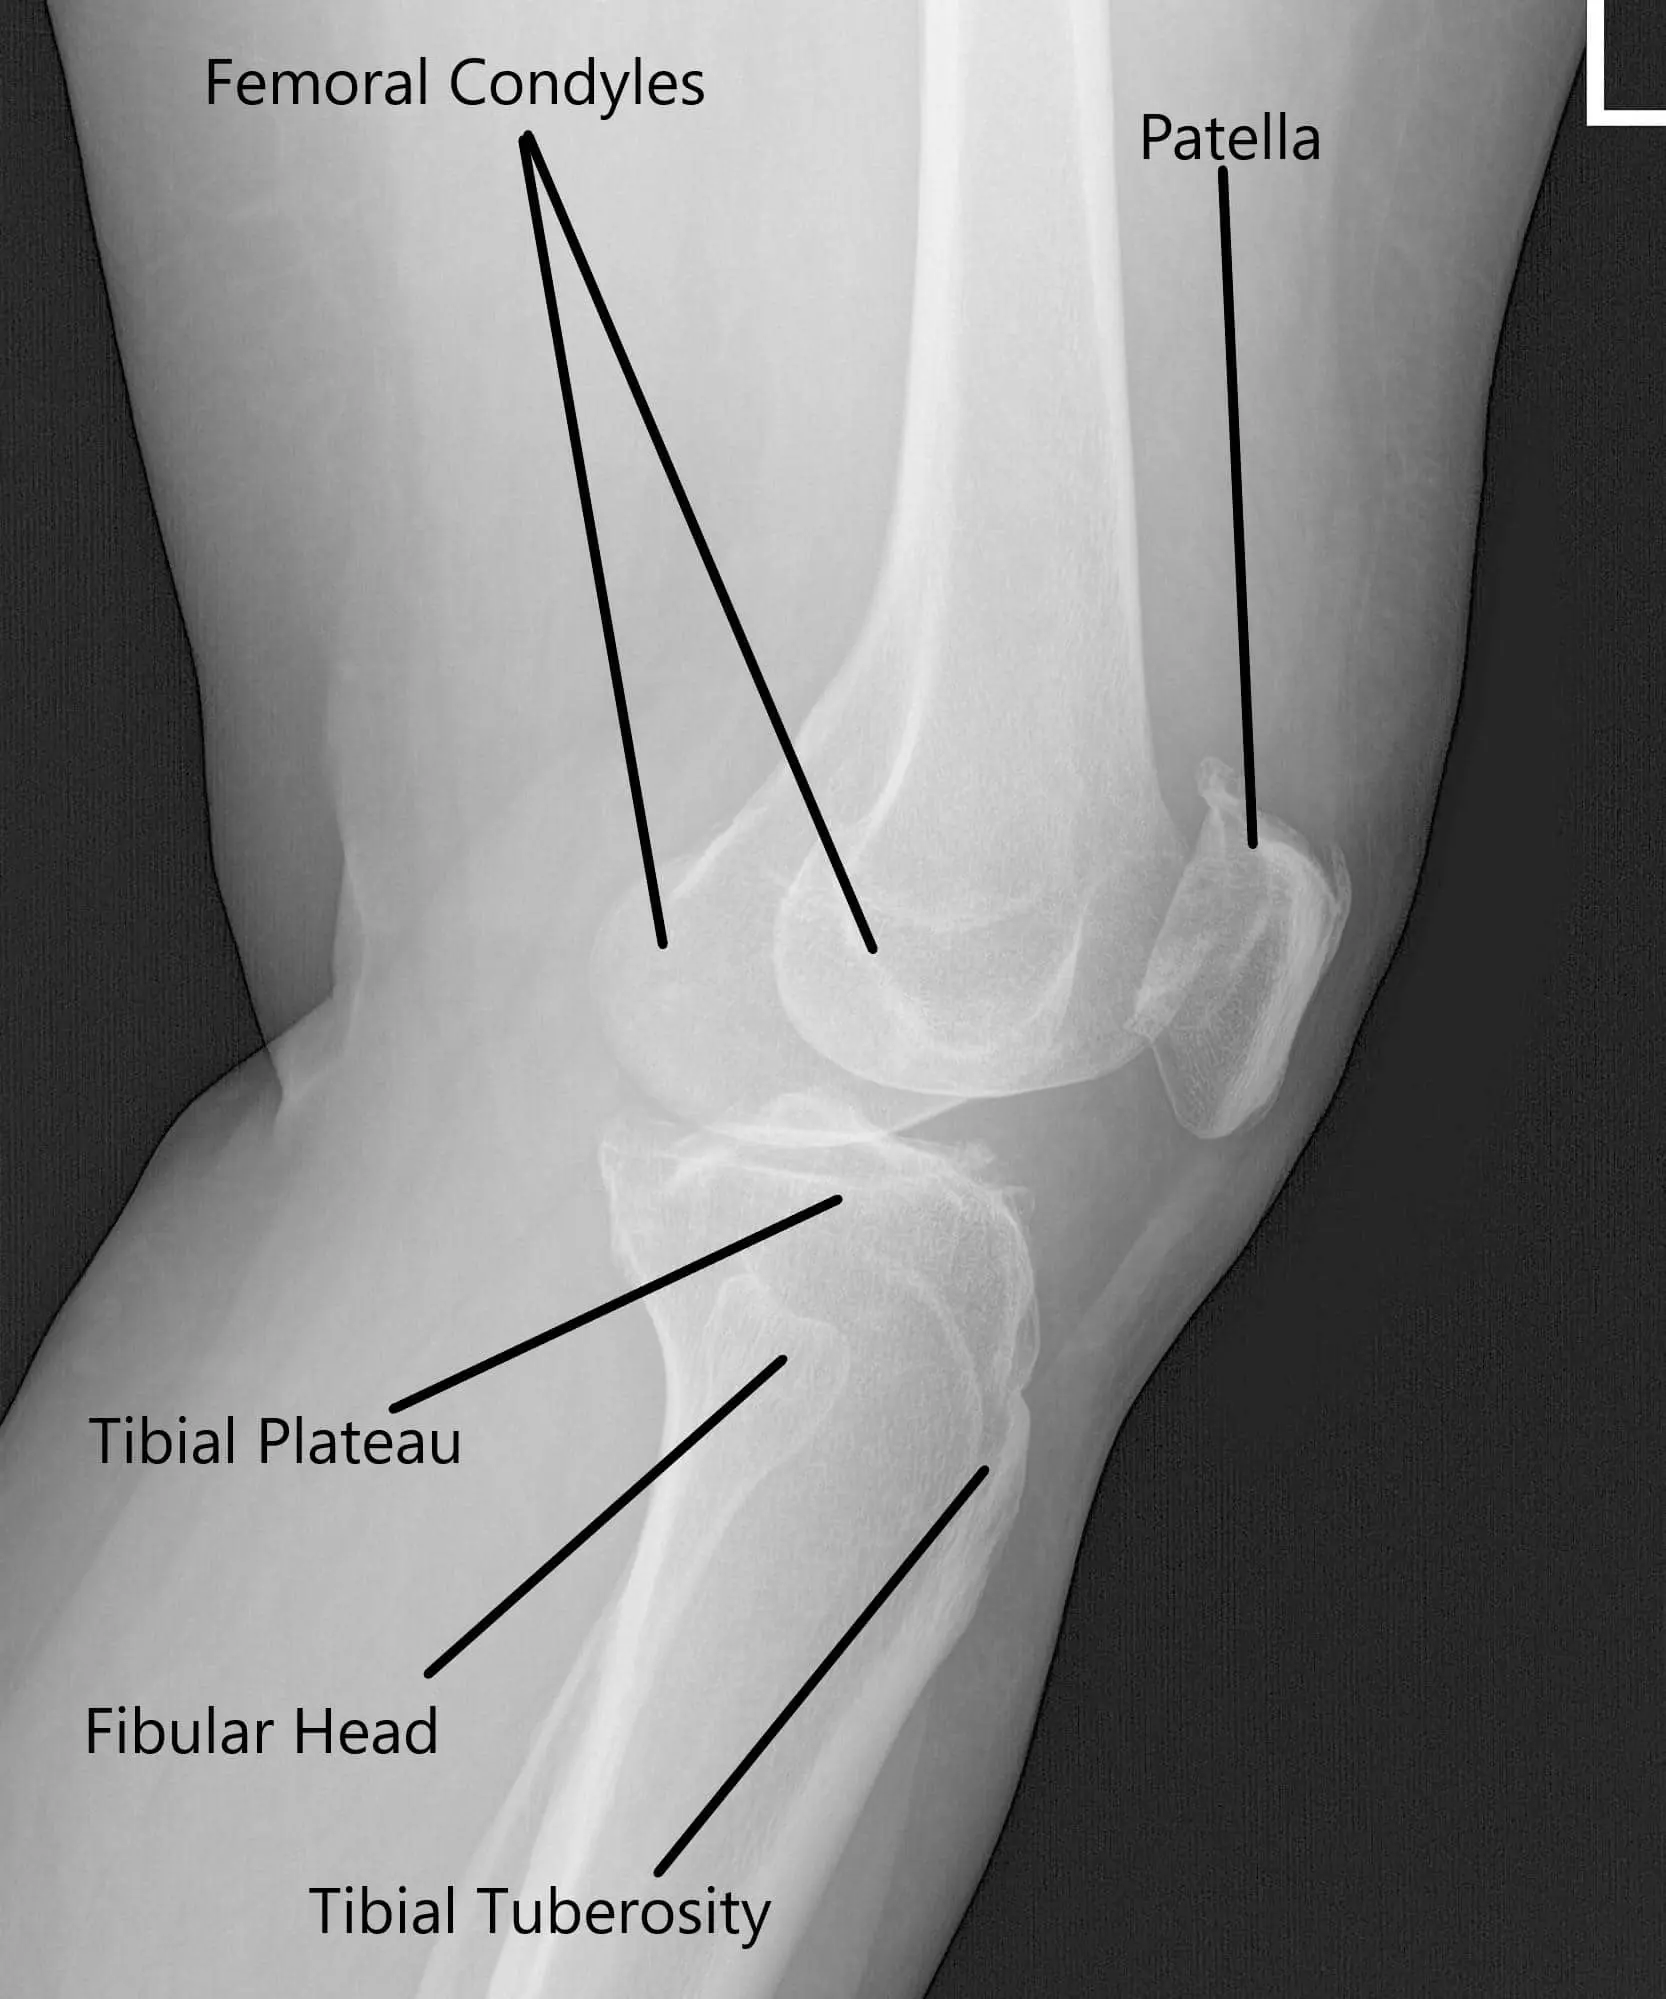

Radiografía de la rodilla izquierda que muestra las vistas AP y lateral.